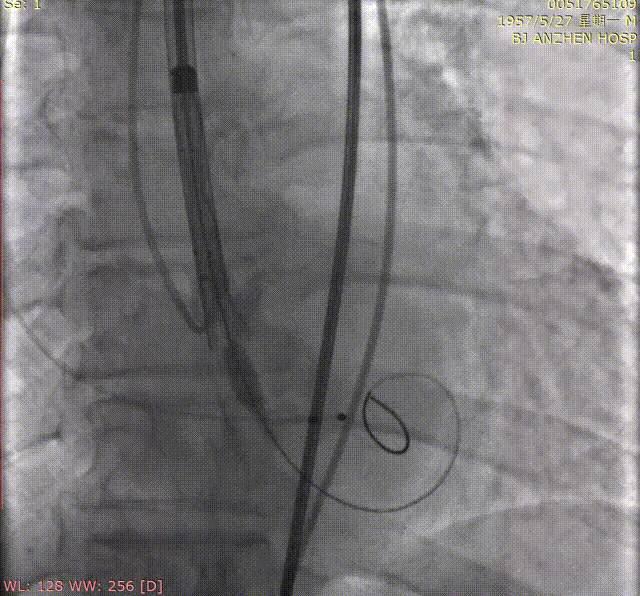

8.沿导丝送入4mm*20mm球囊预扩张后,植入6*18mm支架一枚,再次造影提示支架位置良好,狭窄解除。

肾动脉支架植入